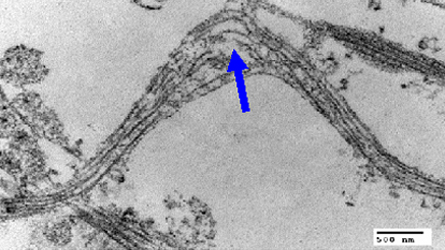

Recently, researchers have found that sudden blows can cause damage to the long fibers that extend from brain cells called axons, sometimes breaking the links between brain cells. But researchers didn’t know exactly what inside the axon snapped. The new research, conducted by Douglas Smith of the University of Pennsylvania and colleagues, finds that tiny tracks called microtubules are damaged inside axons by forces similar to those that cause traumatic brain injury.

Microtubules extend down the length of axons and serve as “superhighways of protein transfer,” says Smith. Brain cells rely on microtubules to move important cellular material out to the end of the axons. When Smith and colleagues quickly stretched brain cells growing on a silicone membrane, the microtubules inside the axons immediately buckled and broke, spilling their contents. “This disconnection at various discrete points spells disaster, and things are just dumped out at that site,” Smith says. “Microtubules are the stiffest component in axons, and they can’t tolerate that rapid, dynamic stretch.”